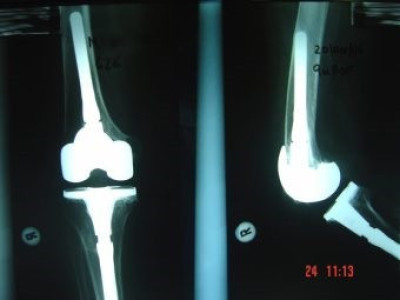

Revisión de prótesis de rodilla

Envíado por Dr. Ricardo Antonio Gómez G.